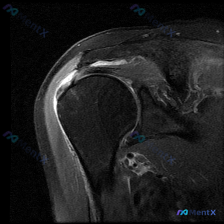

刚整理完一份肩部MRI读片病例,病例本身不复杂,但很容易只看到表面的积液忽略根本问题,分享给大家,整理一下完整的分析思路。 病例影像基础信息 本次读片基于肩部MRI-T2序列冠状位影像,核心初始发现是软组织积液,我们来逐层拆解: 影像学客观发现 1. 冈上肌肌腱:在肱骨大结节附着点(足印区)区域,肌...

最近看到这份肩部MRI病例,问题问的是影像里的软组织积液怎么解释,整理了完整的读片和分析思路分享给大家。 一、影像基本信息 这是一张肩关节冠状位T2序列MRI,扫描范围覆盖肩峰、肩锁关节、冈上肌肌腱、肱骨头、肩关节间隙和三角肌,我们先明确正常信号基准:T2序列正常肌腱是低信号(黑色),关节液、水肿是...